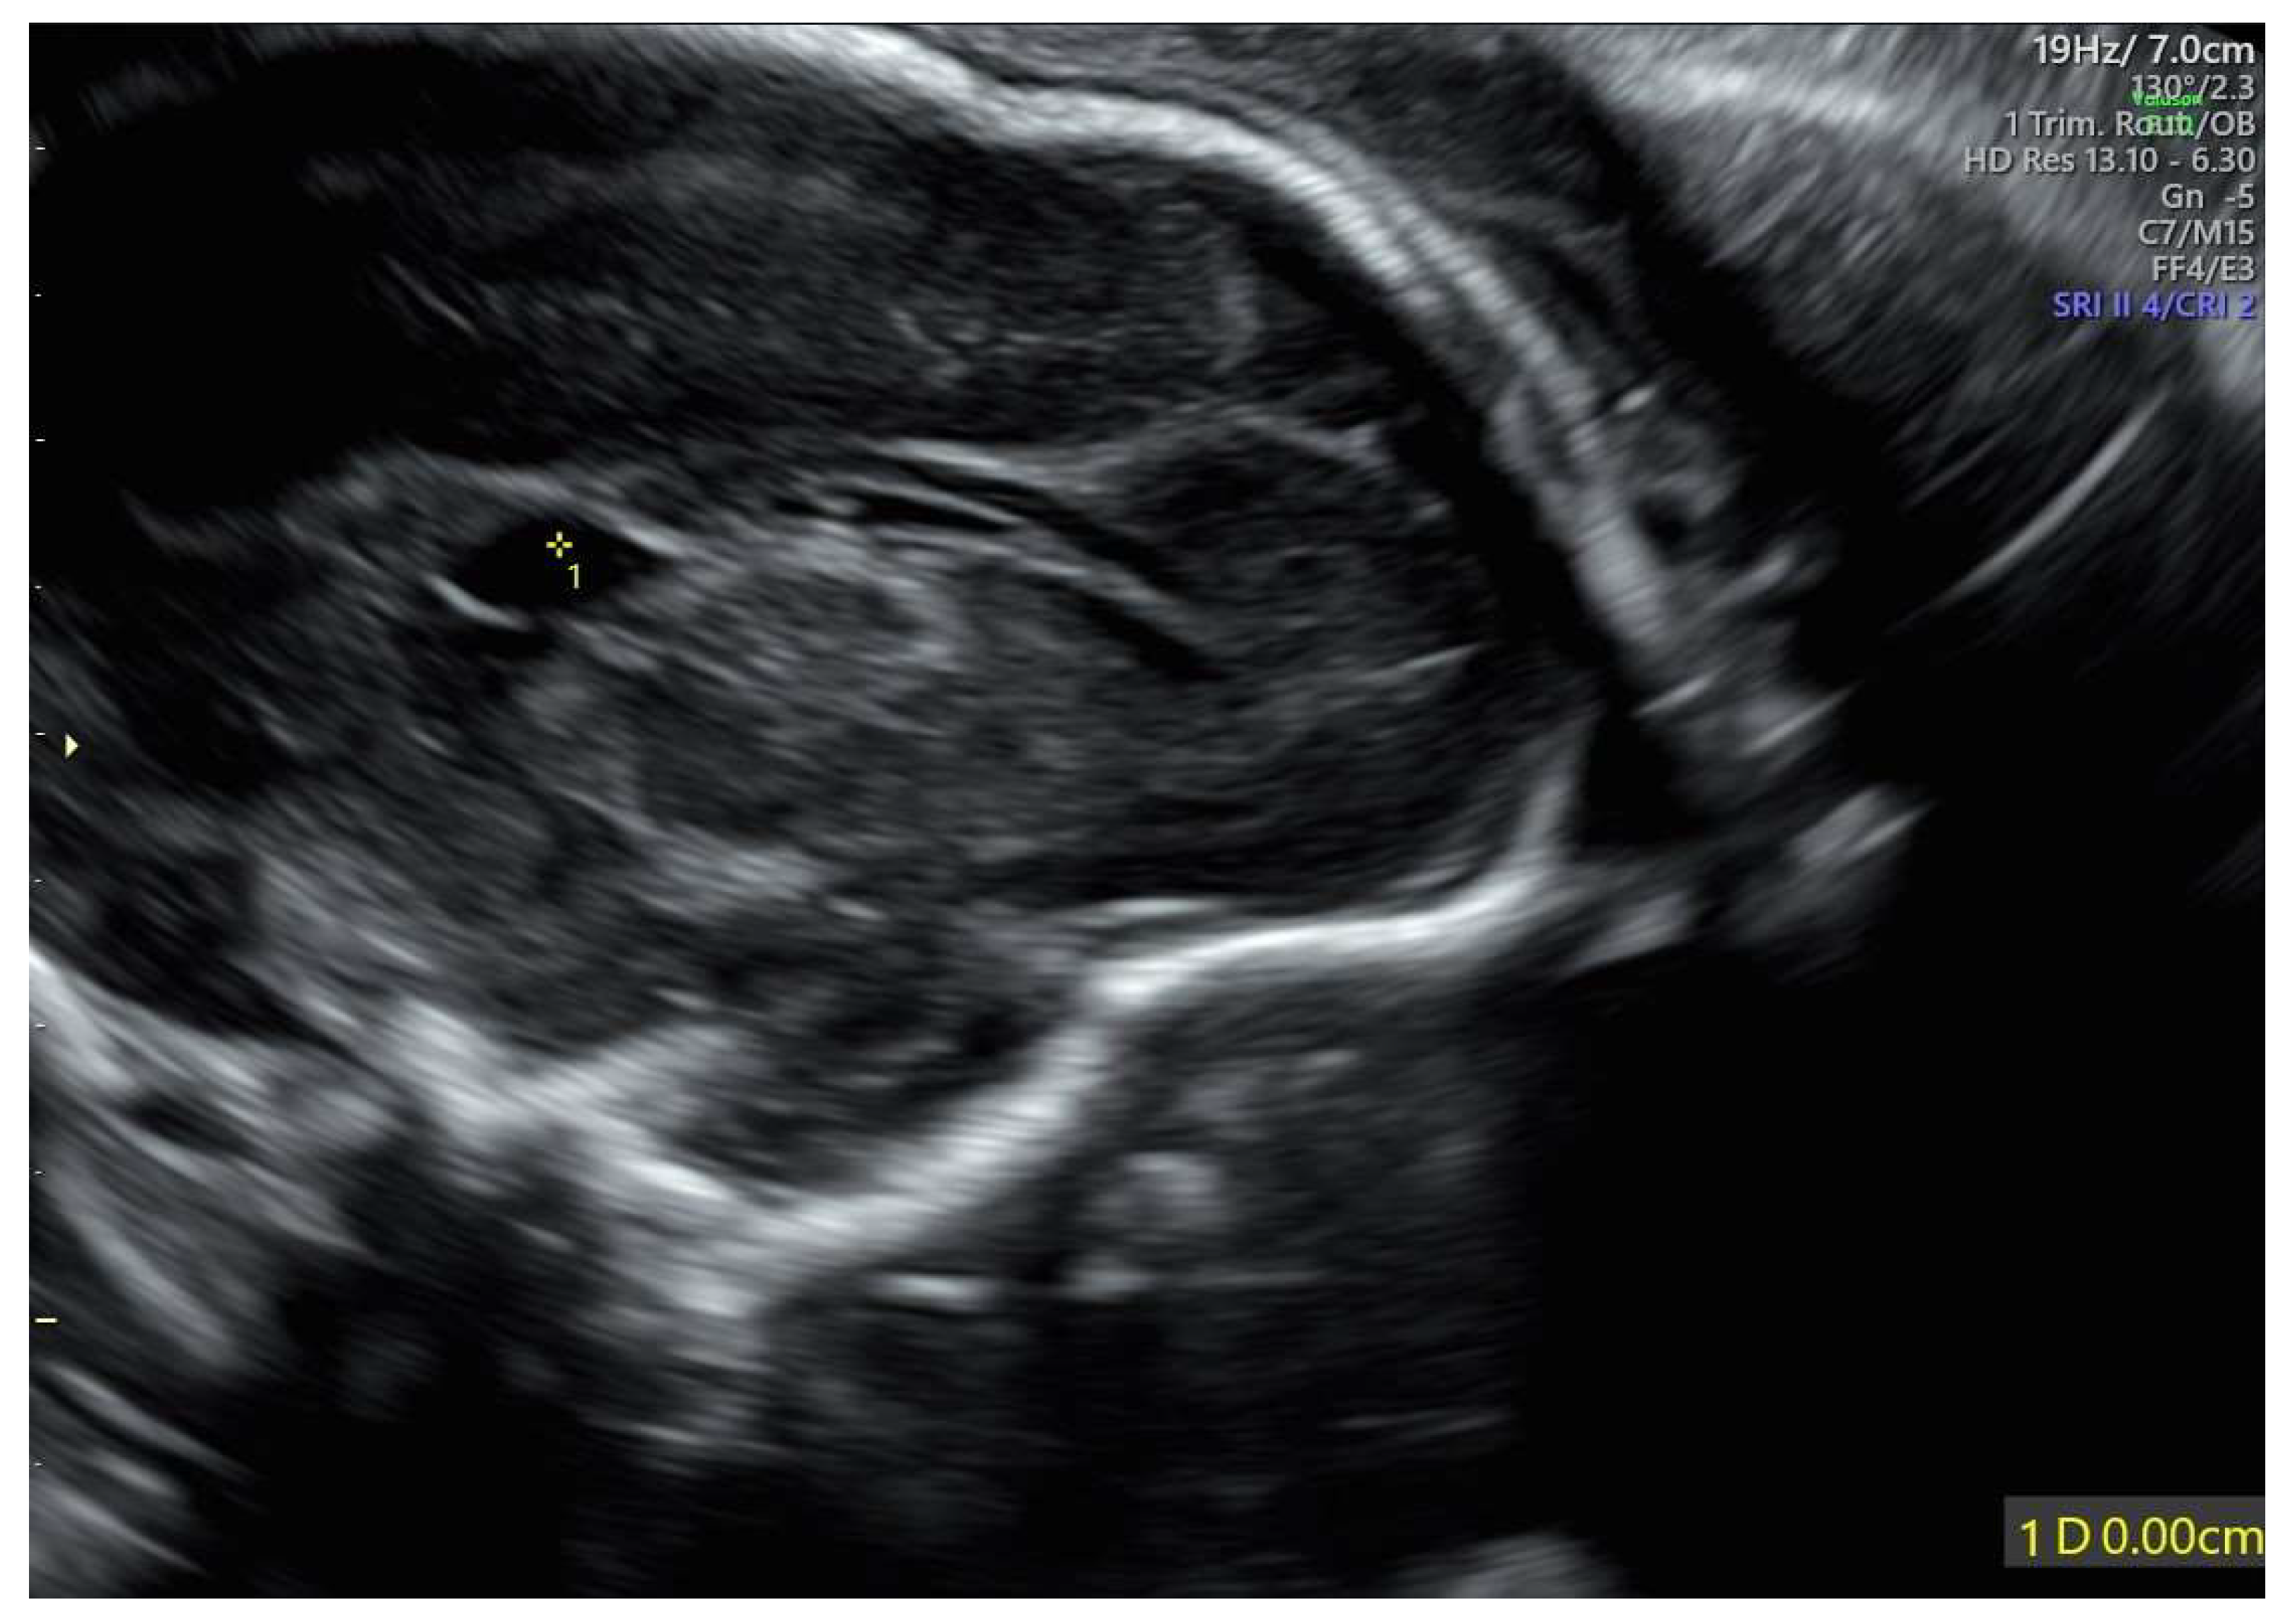

A 35-year-old mother, gravida 2, para 1, regularly attended the scheduled US scans for the first trimester. At 13 weeks of gestation (wg), the US showed no anomalies, and the nuchal translucency (NT) was of 2.12 mm. The Harmony™ non-invasive prenatal test (NIPT) showed a low risk for trisomies 21, 18, and 13. The patient presented at 21 weeks + 3 days for the planned morphological scan of the second trimester. The US showed oligo/anhydramnios, IUGR (fetal measurements below the 1st centile), a velum interpositum cyst, and mild pericardial effusion. The longitudinal diameter of both kidneys was within the normal centile for the gestational age, the left measuring 19.3 mm and the right, 20.5 mm, respectively (Figure 1) [12].

Figure 1.

Fetal US at 21 weeks + 3 days: both kidneys presented a longitudinal diameter within the normal centile for the gestational age, measuring 19.3 mm on the left (A) and 20.5 mm on the right (B).

In our case, the US findings, at 21 weeks + 3 days, included IUGR, oligo/anhydramnios, velum interpositum cyst, and mild pericardial effusion. Despite oligo/anhydramnios, both kidneys were not hypoplastic, measuring in longitudinal diameter 19.3 mm on the left, and 20.5 mm on the right, respectively [12].